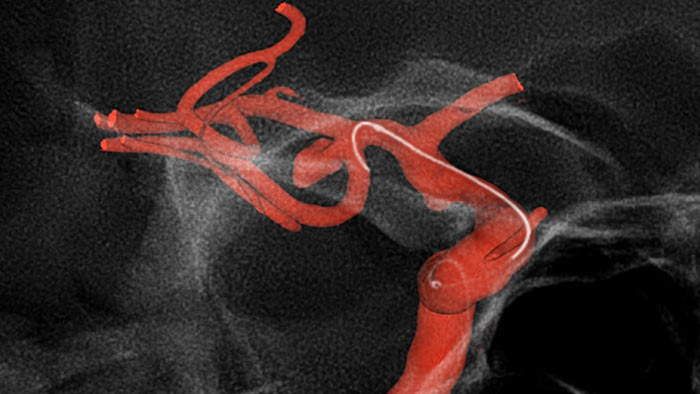

O SmartCT Roadmap melhora a visualização de vasos sobrepostos para suportar uma navegação precisa do fio-guia e do cateter através do sistema vascular complexo. Oferece uma precisão de alto nível com compensação em tempo real para pequenos movimentos da gantry, da mesa e dos pacientes.

O Roadmap Pro é um mapa avançado de duplo contraste que ajuda a melhorar a visibilidade dos vasos sobrepostos enquanto equilibra a exposição às radiações. Pode ser personalizado para mostrar o avanço durante a colocação da bobina.